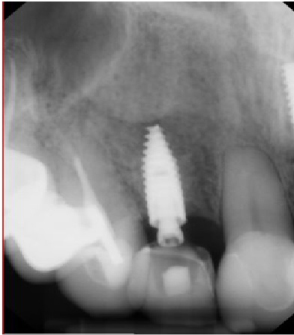

Using bilateral papillae sparing releasing incisions at surgical sites, the Cytoplast® membranes and tacks were removed and the implant sites were prepared showing excellent bone regeneration (Figures 20, Figure 21, and Figure 22). Standard protocol was used to prepare Straumann® Bone Level Tapered implants (Andover, MA, USA). (Figures 20 and Figure 22). Four months post implant placements with all 3 implants osseointegrated and provisional restorations in place. (Figures 23, Figure 24, and Figure 25).

Figure 23: 4-month post-op implant placement #7, implant osseointegrated, provisional restoration in place. View Figure 23

Figure 24: 4-month post-op implant placement #9, implant osseointegrated, provisional restoration in place. View Figure 24

Figure 25: 4-month post-op implant placement #10, implant osseointegrated, provisional restoration in place. View Figure 25